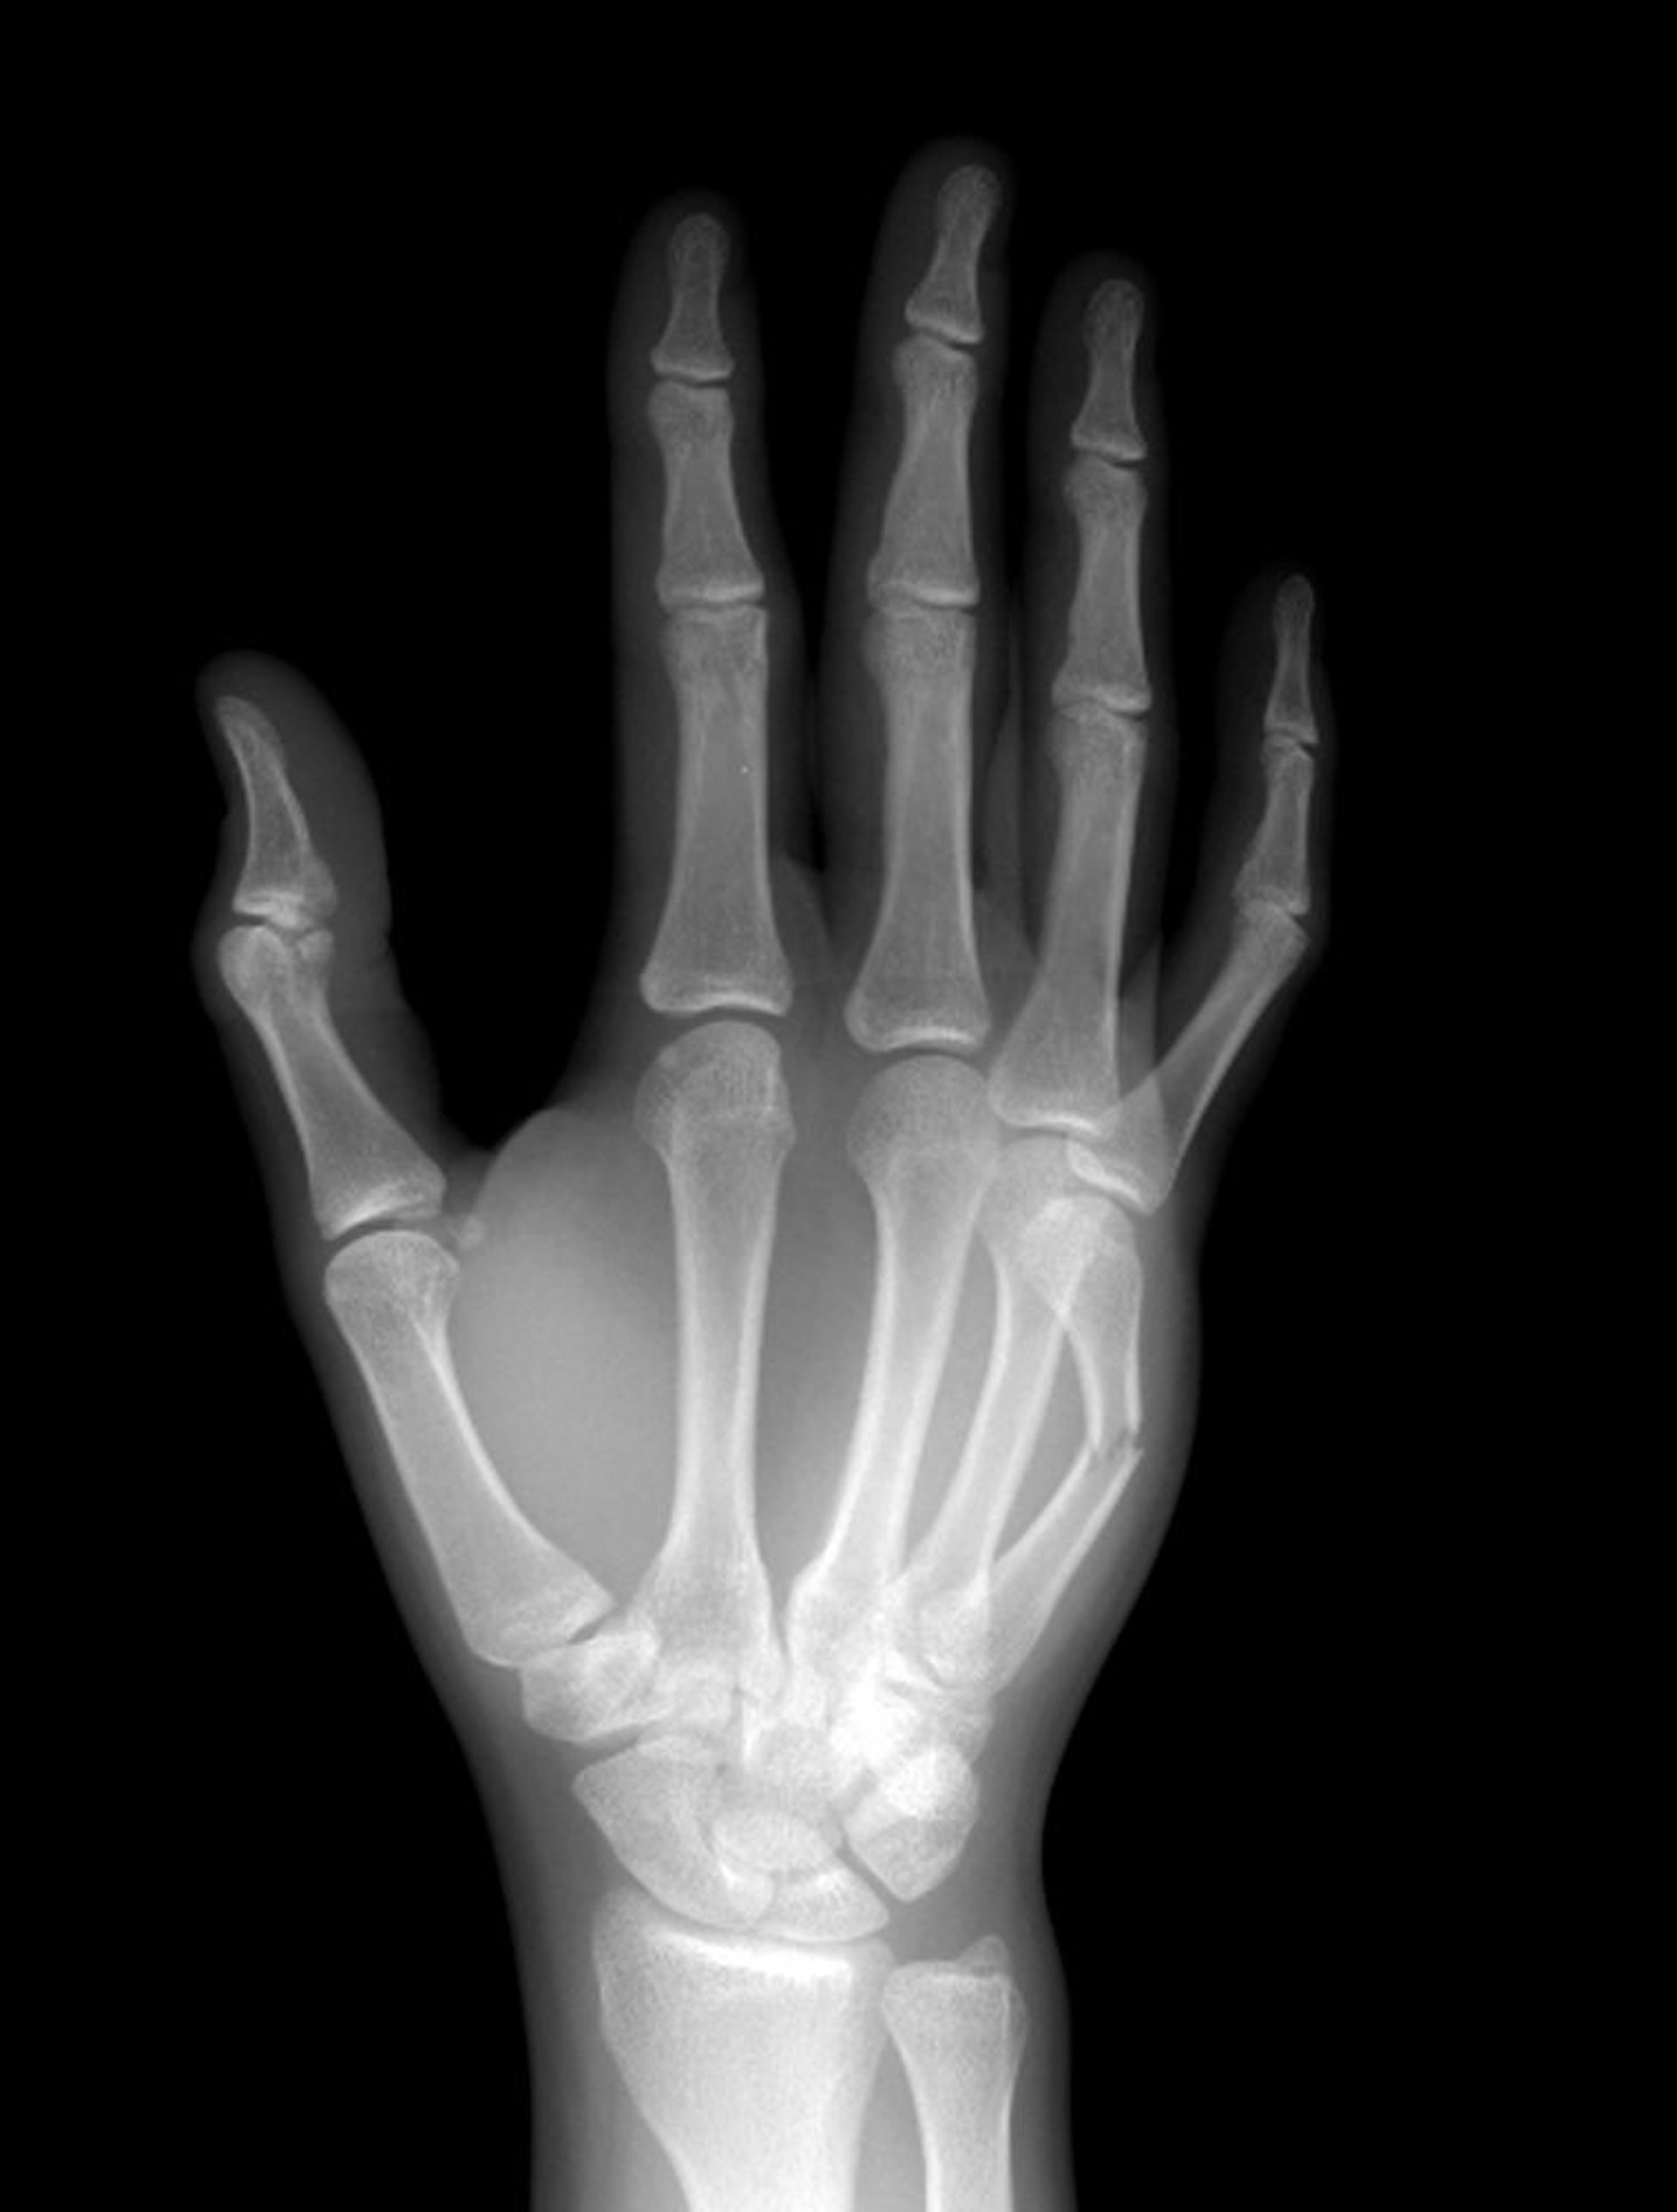

Переломы шейки пястных костей

Шейка V пястной кости сломана в среднем отделе.